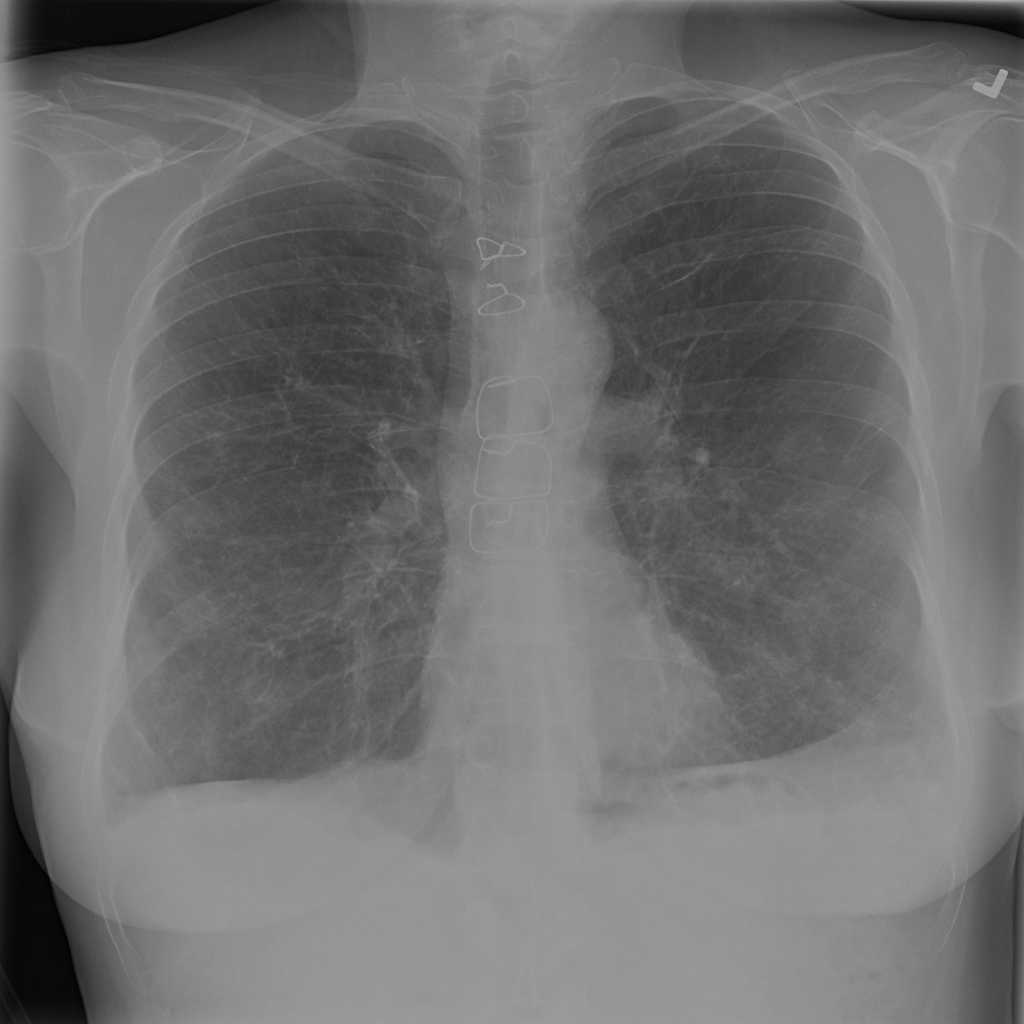

PAT-E066 · IMG-010Fibrosis

PAT-E066 · IMG-010

PA